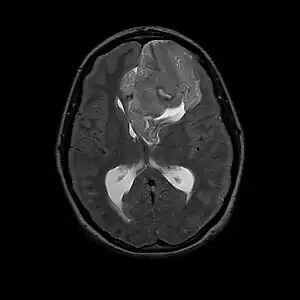

Neurocytoma is a type of nervous system benign tumor which is primarily derived from nervous tissue.[1]